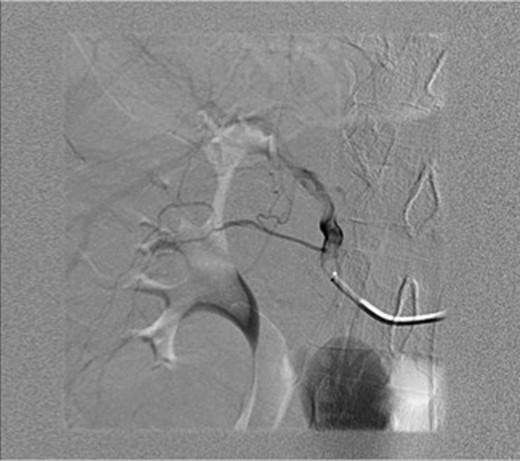

An ultrasound was done showing a mass in the right upper quadrant with no visualization of the gallbladder and no evidence of biliary tree dilatation. Therefore, a CT scan was performed which showed a large haematoma in the gallbladder fossa, which distends the gallbladder wall causing mass effect (Fig. 1a and b). Furthermore, active extravasation of IV contrast was seen. Initially, this was not clear if the haematoma is arising from the liver or within the gallbladder. Given his haemodynamic stability he was taken to the interventional angiography suite for an arteriogram of his abdominal aorta and splanchnic vessels. The bleeding was localized to a branch of the cystic artery and no pseudoaneurysm was identified (Fig. 2). Then, embolization of cystic artery with gelfoam material was performed. Since, embolization of the cystic artery proper was done, the decision was made to explore the patient and perform a cholecystectomy. Prior to the operation the patient became tachycardic at 100 with a systolic blood pressure of 90 and a diastolic of 60. His repeat haemoglobin was 10.1. Appropriate resuscitation with blood transfusion was performed.

Arteriogram of abdominal aorta and splanchnic vessels showing localized bleeding in a branch of the cystic artery and no pseudoaneurysm.

A possible explanation for the intraperitoneal rupture in this case would be the possibility of fibrosis at the ampulla due to the patient history of PSC requiring frequent endoscopic retrograde cholangiographies. This could have caused the retrograde accumulation of blood in the gallbladder and biliary system rather than bleeding into the intestine. In this case angiography was helpful in localizing the bleeding, and since an embolization of the cystic artery proper was done, an urgent cholecystectomy was indicated even though a perforation was not seen on preoperative investigation.